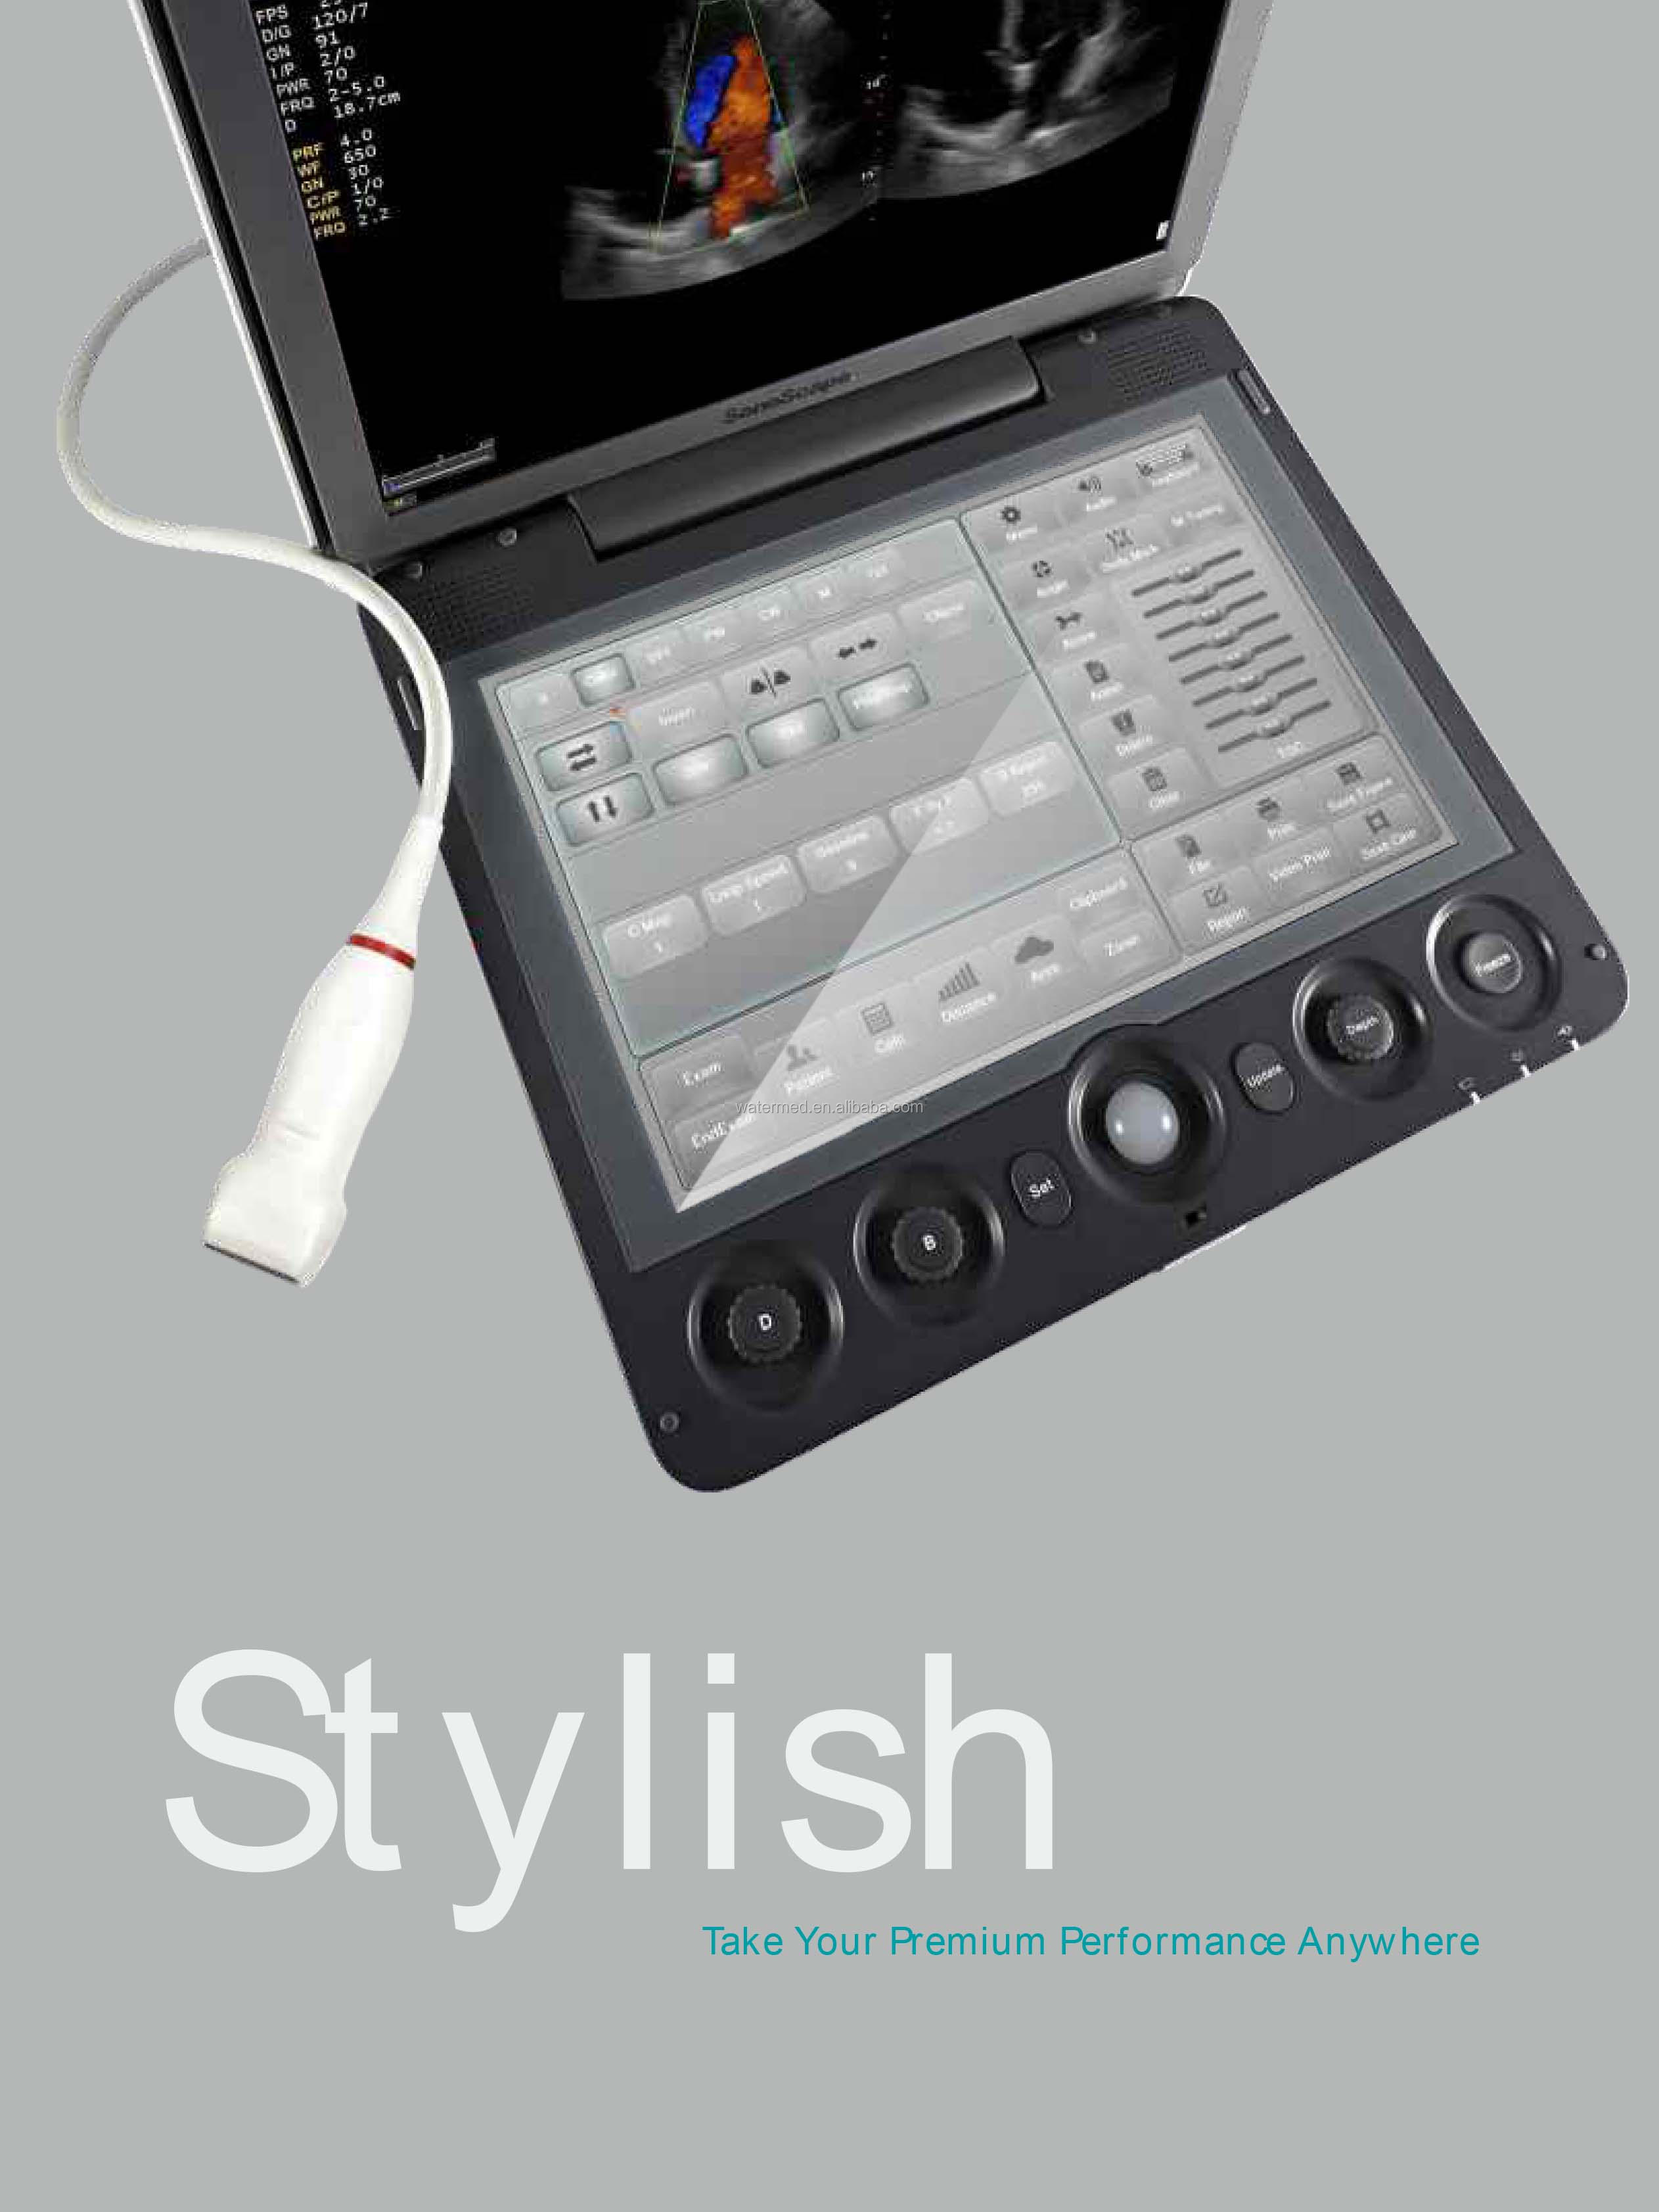

touch screen | 13.3 inches (135° variable) | ||||||

SonoScape has been in the field of ultrasound since releasing the first portable color Doppler ultrasound system. From this dedication, a large number of ultrasound technologies have emerged, especially in hand-held systems. Out of this dedication, the S9 was released as a powerful and versatile imaging platform with a futuristic design. Small in size and wide in application, the S9 is suitable for Cardiology, Radiology, Abdominal, Obstetrics, Small Parts and Urology, providing the best solution for ultrasound imaging with outstanding performance.